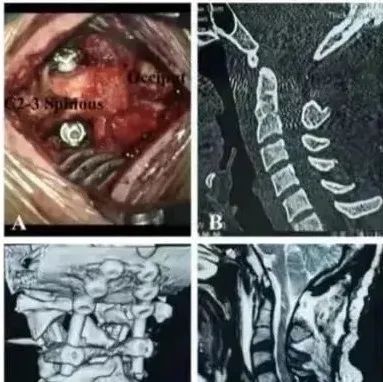

【手术技术创新】三博脊柱开辟颈2椎体关节面下螺钉置钉技术和经验总结在国际期刊发表

近日,首都医科大学三博脑科医院脊髓脊柱外科中心主任范涛教授团队开辟“颈2椎体关节面下螺钉应用于颅頸交界区畸形手术的经验总结”在国际期刊《Journal of orthopedic Surgery and Research》(IF 2.68)上在线发表。该置钉方法结合C1-2关节间松解复位技术,再联合使用三博脊柱原创的滑轨牵引头架,可使更多复杂颅颈交界区畸形寰枢椎脱位手术进一步路径清晰、便捷高效与安全可靠。...